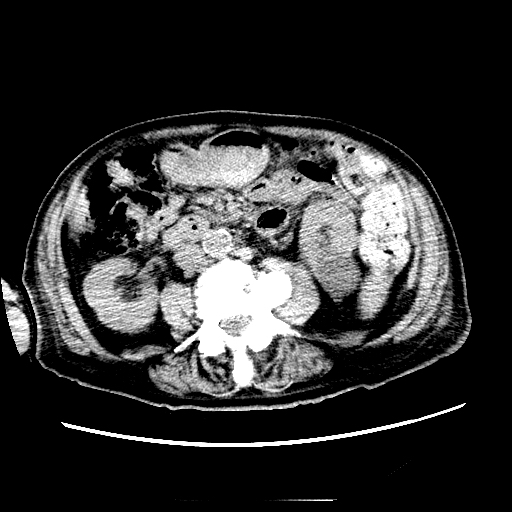

Case Presentation: An 87 year old male with a history HFrEF 35%, BPH, Afib, seizure disorder. He had a recent fall and presented with A-fib with RVR. His creatinine at that time was found to be 5.6 (no baseline creatinine at that time). Renal and bladder ultrasound showed large intravesical mass consistent with bladder mass versus prostate mass versus clot. Foley catheter was placed and kidney function improved after bladder irrigation. Pt was discharge to NH. Creatinine at time of discharge was 2.9. In nursing home he had vomiting and was found to be very lethargic, having metallic taste in mouth and decrease in urine output. Pt denied fever, chills, cough, SOB. Blood work showed Creatinine of 6.5 with metabolic acidosis. Urine sediment showed few coarse granular casts. Pt underwent one session of dialysis. Lab work up showed lymphocytosis, anemia, and free light chains were positive. Imaging studies showed splenomegaly and retroperitoneal lymphadenopathy. Given the unclear nature of his AKI he underwent kidney biopsy that showed infiltration of the kidney with lymphocytes and chronic parenchymal changes with 46% global Glomerulosclerosis CD20 and CD5 positive and flow cytometry of the peripheral blood reveals CLL, suggesting that lymphoma is the likely etiology of his renal failure. He was started on steroids and showed improvement of his renal function.